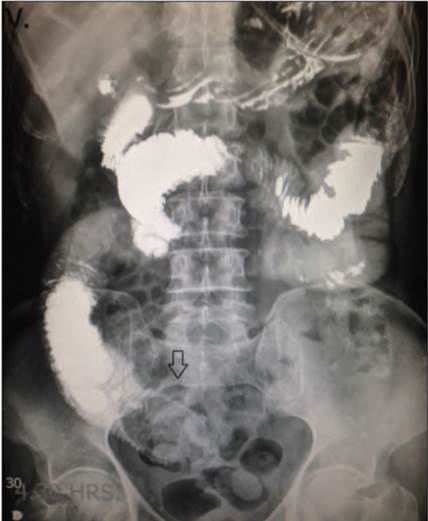

Ingresa a piso de cirugía general con diagnóstico de oclusión intestinal, manejado de manera conservadora durante 48 h con mejoría parcial y tolerancia a la vía oral, 12 h después inicia nuevamente con datos de oclusión intestinal. Se solicita tránsito intestinal, donde presenta imagen radioopaca ovoidea a nivel de fosa ilíaca derecha ocluyendo el 90% de la luz del intestino delgado, ocasionando dilatación de intestino proximal (figura 2). También se realiza tomografía de abdomen con dilatación de intestino delgado y presencia de imagen ovoidea a nivel de fosa ilíaca derecha (FID), sugestivo de íleo biliar. El diagnóstico se estableció 4 días posteriores a su ingreso. Es programado para laparotomía exploradora y enterolitotomía, con presencia de lito impactado en yeyuno a 100 centímetros (cm) del ángulo de Treitz; se realiza enterolitotomía transversal a 10 cm del sitio de la obstrucción en el borde antimesentérico, se extrae lito de 7 × 4 × 3 cm (figuras 3 y 4), posteriormente se realiza enterotomía en 2 planos (figura 5). Se inicia dieta líquida en su quinto día posquirúrgico, con adecuada tolerancia a la vía oral. Egresa a su domicilio al séptimo día posquirúrgico. Actualmente el paciente se encuentra asintomático, en protocolo para colecistectomía y reparación de fístula bilioentérica.

Figura 2 Tránsito intestinal con imagen ovoidea en intestino delgado que impide el paso del medio de contraste. 4:30 h posterior a la ingesta del medio de contraste (flecha).